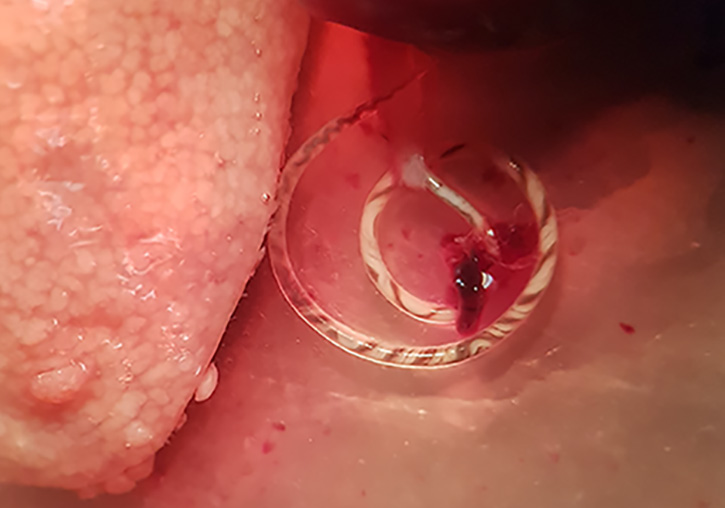

Una investigació liderada pel grup Paràsits i Salut de la Universitat de València ha trobat per primera vegada a Europa continental el nematode (cuc) Angiostrongylus cantonensis, un paràsit zoonòtic (capaç de ser transmès a l’ésser humà) present a les artèries pulmonars de les rates i que és l’agent causal més comú a l’ésser humà de la meningitis eosinofílica (ME). Aquesta malaltia provoca una inflamació de la membrana que cobreix el cervell i pot causar atacs, lesions cerebrals i trastorns visuals, entre d’altres símptomes.

El grup de recerca Paràsits i Salut, del Departament de Farmàcia i Tecnologia Farmacèutica, i Parasitologia de la Facultat de Farmàcia, treballa en col·laboració amb el Servei de Sanitat de l’Ajuntament de València i l’empresa Laboratorios Lokímica –responsable del control de plagues–, en un estudi parasitològic dels rosegadors a València. El descobriment, de repercussió important en Salut Pública, del nematode s’ha donat tant en rates de claveguera (Rattus norvegicus) com en la rata negra (Rattus rattus).